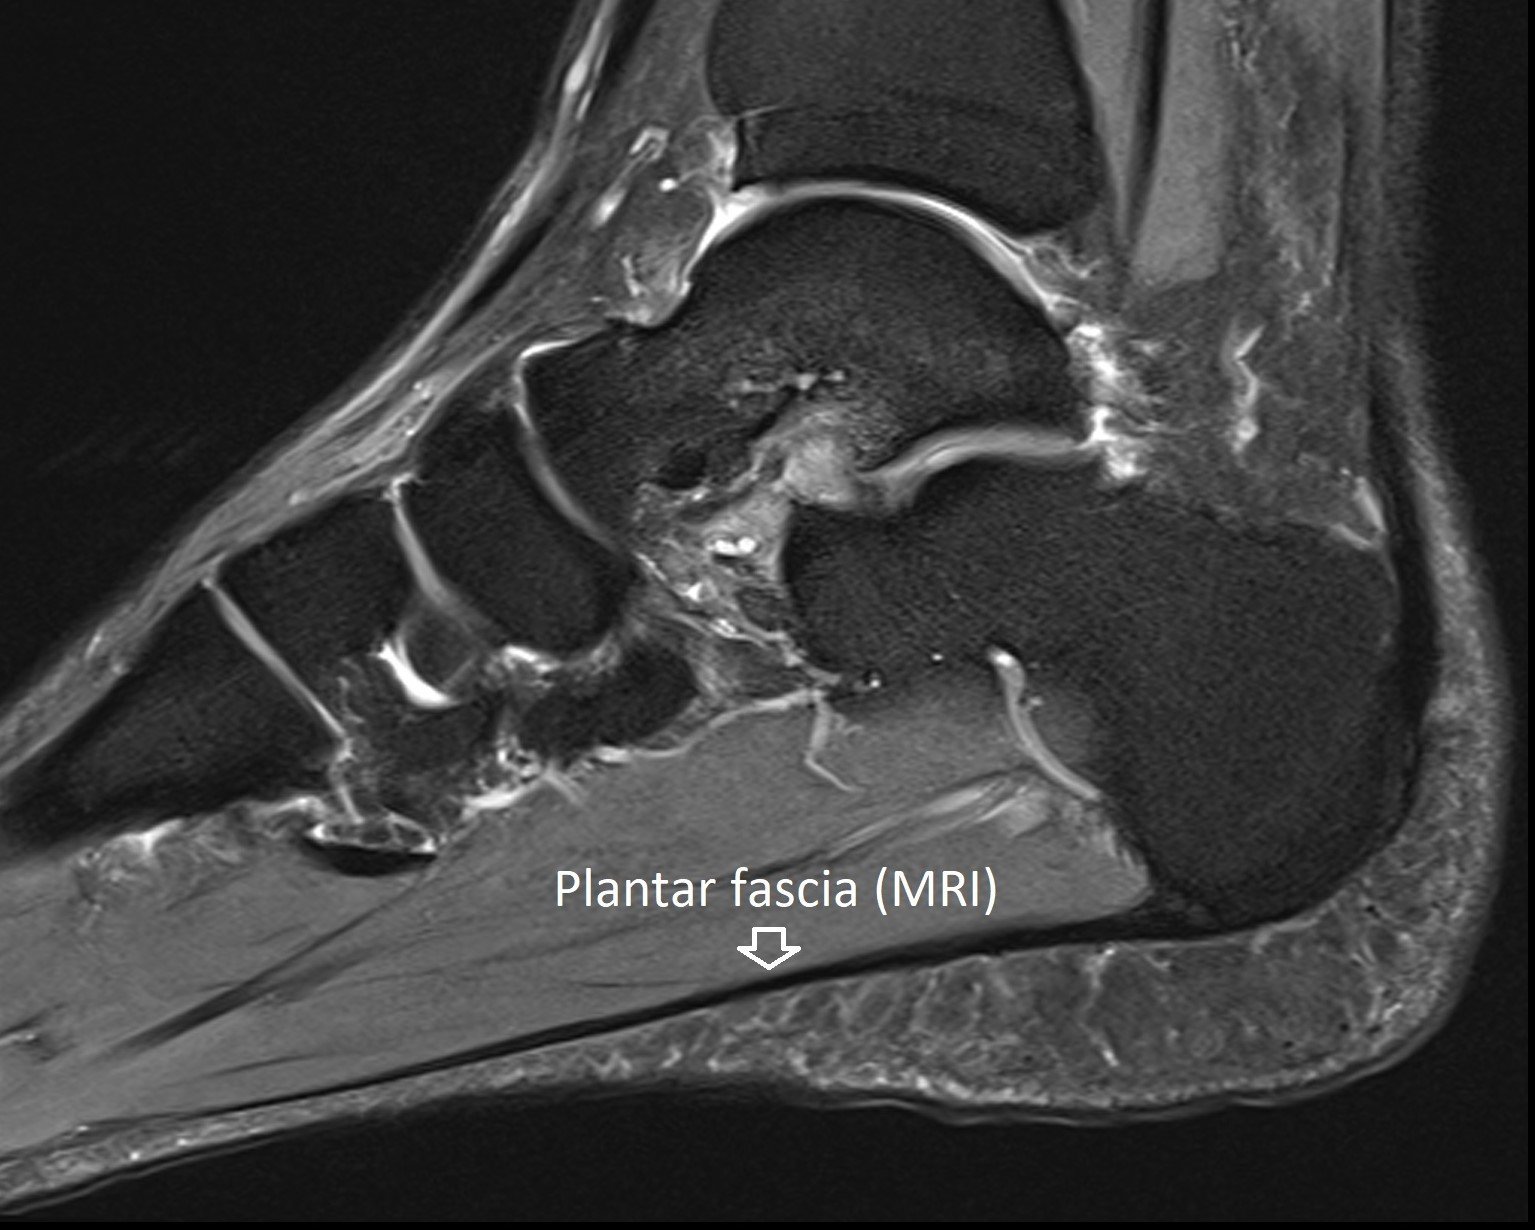

Plantar Fasciitis X Ray . Plain radiography is helpful in ruling out bony lesions. This review article aims to provide simple and systematic. Extracorporeal shock wave therapy is a well established treatment for kidney stones. imaging is often required to confirm diagnosis. learn how to diagnose plantar fasciitis and its complications with mri. See cases of acute rupture, chronic. A calcaneal spur is frequently seen on lateral heel. people with plantar heel pain are more likely to have a thickened plantar fascia, abnormal plantar fascia tissue, a. extracorporeal shock wave therapy.

Plantar Fasciitis X Ray imaging is often required to confirm diagnosis. Extracorporeal shock wave therapy is a well established treatment for kidney stones. A calcaneal spur is frequently seen on lateral heel. learn how to diagnose plantar fasciitis and its complications with mri. This review article aims to provide simple and systematic. imaging is often required to confirm diagnosis. See cases of acute rupture, chronic. people with plantar heel pain are more likely to have a thickened plantar fascia, abnormal plantar fascia tissue, a. extracorporeal shock wave therapy. Plain radiography is helpful in ruling out bony lesions.